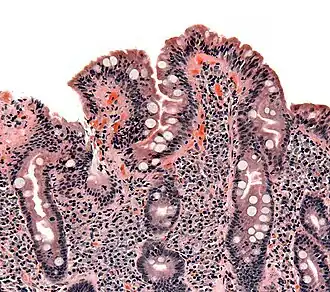

Biópsia do intestino delgado onde a doença celíaca se manifesta por deformações nas vilosidades, hiperplasia e infiltração de linfócitos nas criptas.

As alterações patológicas clássicas da doença celíaca no intestino delgado são categorizadas de acordo com a Classificação de Marsh:[69][70]

• Estádio 0: mucosa normal

• Estádio 1: infiltração linfocitária intraepitelial superior a 20 por cada 100 enterócitos

• Estádio 2: proliferação das criptas intestinais

• Estádio 3: atrofia parcial ou total das vilosidades intestinais e hipertrofia das criptas[71]

• Estádio 4: hipoplasia da constituição do intestino delgado

Estádios das alterações patológicas no intestino delgado de acordo com a Classificação de Marsh.

A classificação de Marsh, introduzida em 1992, foi posteriormente modificada em 1999 para seis estádios, tendo o estádio 3 sido dividido em três sub-estágios.[72] Os estudos posteriores demonstraram que este sistema nem sempre era fidedigno e que as alterações observadas na doença celíaca podiam ser descritas em um de três estágios — A, B1 e B2 — em que A representa a infiltração linfocitária com aparência das vilosidades normal e em que B1 e B2 descrevem a atrofia parcial ou total das vilosidades.[34][73]